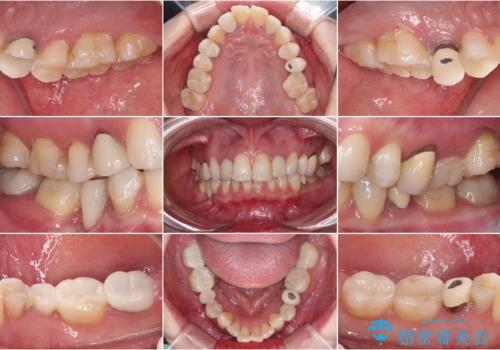

- クラウンから金属の土台が見えてきてしまったとのことで、作り替えを希望して来院された患者様です。

前歯や金属が露出している歯、痛みを感じる歯を中心に、オールセラミッククラウンにて補綴治療することとしました。

以前はセラミッククラウンのフレームとして金属が使用されており、歯肉の経年変化やセラミックのすり減りなどにより、金属が見えるようになってくることがあります。

現在は金属の代わりに強化セラミックを使用したオールセラミッククラウンが主流です。金属色が気になる方はご相談ください。